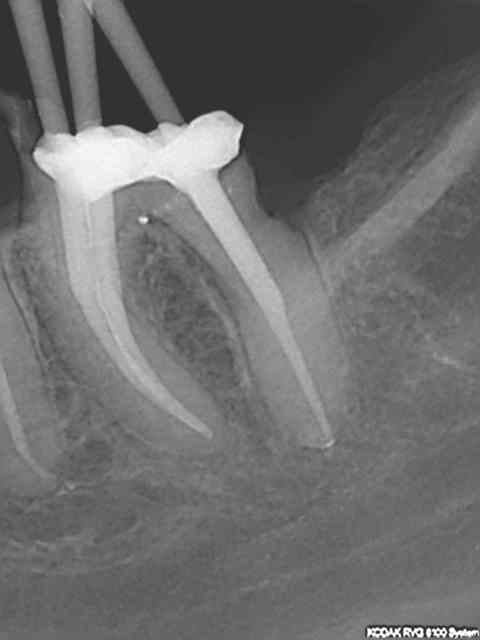

Et une de plus !

R19 vxiysf - Eugenol

R20 kboz6l - Eugenol

01 ukhwbq - Eugenol

C'est pas de la frime hein, mais ca fait plaisir d'avoir trouvé ENFIN une technique rapide et reproductible sans casse. (enfin presque il y a dans le tas un micro morceau de R25 pas loin de l'apex )

Bravo ! Belles images